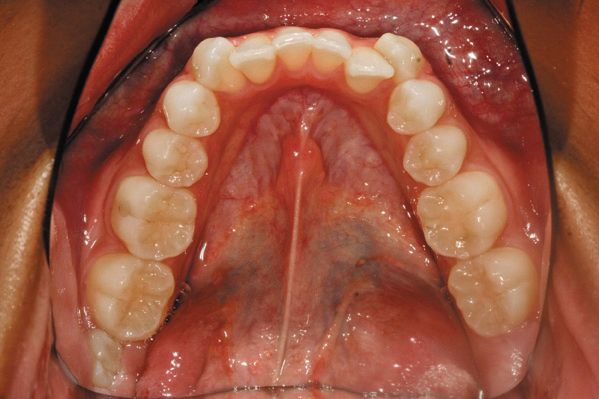

Fig. 6: Lower full arch mirror photo.

The final two photos are of the maxillary occlusal and mandibular occlusal frame. The main emphasis of these shots is to not leave any teeth out of the photo. Focusing the camera in the center of the plate and keeping the nose out of the frame completes these images.